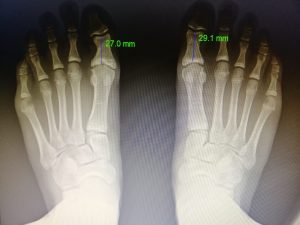

Diagnóstico por imagen de deformidades, fracturas, procesos degenerativos que afectan a los huesos.